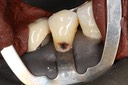

Larry Fujioka #29,30 with dam

Larry Fujioka #29,30 caries removal

Larry Fujioka #29,30 buccal view